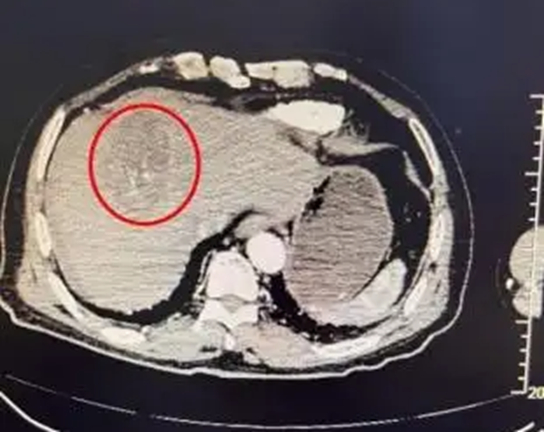

Kết quả khám cấp cứu cho thấy một khối u lớn, kích thước khoảng 96x68 mm, nằm ở thùy gan trái của bà Lý, đã bị vỡ, gây chảy máu ổ bụng và tích tụ dịch đáng kể quanh gan. Dựa trên tiền sử bệnh, bà được chẩn đoán mắc bệnh u gan ác tính vỡ. Các bác sĩ chỉ ra rằng ung thư gan vỡ là một biến chứng cực kỳ nghiêm trọng, khởi phát và tiến triển nhanh chóng, có thể đe dọa tính mạng do sốc xuất huyết trong thời gian ngắn.